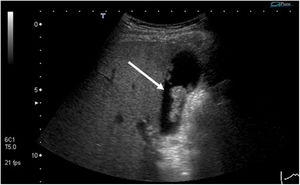

| Pólipo de colesterol | Depósitos de colesterol en el interior de los macrófagos en la lámina propia de la pared vesicular | Estructura hiperecoica, sin sombra acústica posterior y que no varÃa de posición con el movimiento del paciente (fig. 1) |